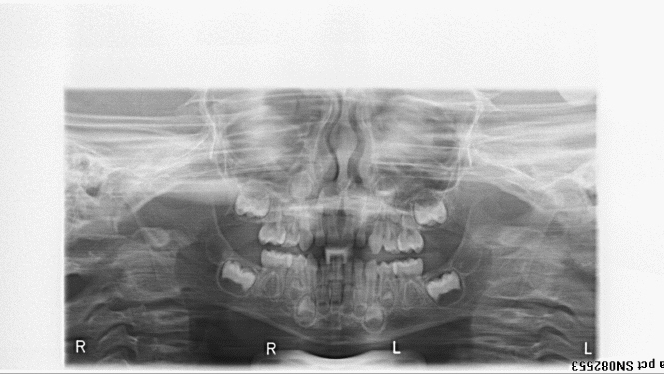

bilan des radiographies début et fin de traitement